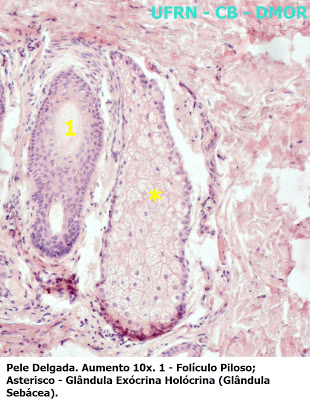

São glândulas localizadas em toda derme, com exceção da pele glabra (sem pelos), na superfície de palmas, plantas e e regiões flexoras dos dedos (Figs 8 e 9). Liberam uma secreção lipídica formada principalmente por triglicerídeos, ácidos graxos livres, ésteres e ésteres de colesterol, mais conhecida como o sebo. O sebo é liberado nos folículos pilosos, na região entre a inserção do músculo eretor do pelo e epiderme. Entretanto, em locais onde não estão presentes folículos pilosos, geralmente na pele fina, a secreção é liberada diretamente na pele, como nos lábios, mamilos, clitóris e pênis. Sua função baseia-se na proteção dos pelos, desestimulação de ectoparasitas e em promover o odor característico do corpo.

Sua classificação se dá em diversos tipos: pelo modo de eliminação das secreções, classificadas como glândulas de mecanismo holócrino, ou seja, o seu produto de secreção é liberado juntamente com toda a célula; e pela sua forma, sendo classificada como uma glândula acinosa simples ramificada, em que vários ácinos secretores se esvaziam em um único canal excretor.

Quando a secreção lipídica fica presa dentro do ducto, isso pode ocorrer por um distúrbio no fluxo da secreção, provocando uma inflamação crônica nos ductos obstruídos e caracterizando um processo chamado de acne, acontecendo comumentemente durante a puberdade. Na imagem abaixo, veja um corte histológico que mostra o folículo piloso e a glândula sebácea.